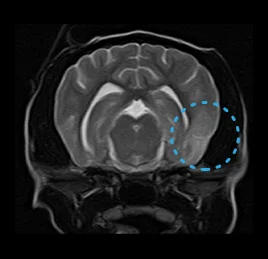

• 수막뇌염

• 허혈성 소뇌경색